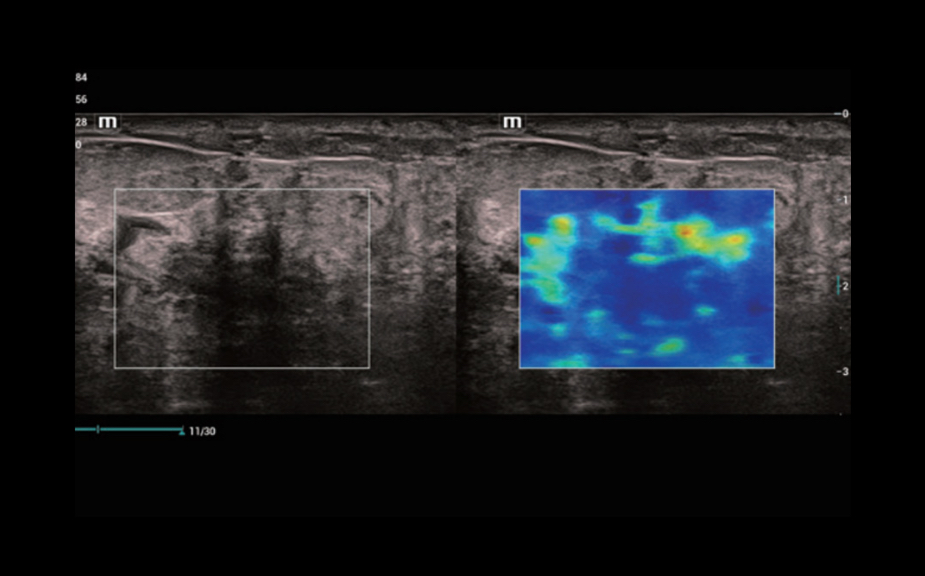

–ù–Ψ–≤–Β–Ι―à–Η–Ι –Ω–Ψ–¥―Ö–Ψ–¥ –Κ –Η–Ζ―É―΅–Β–Ϋ–Η―é ―¹–Ψ―¹―É–¥–Η―¹―²–Ψ–Ι –≥–Β–Φ–Ψ–¥–Η–Ϋ–Α–Φ–Η–Κ–Η: V Flow

–‰―¹–Ω–Ψ–Μ―¨–Ζ―É―é―²―¹―è –Φ–Α―Ä–Κ–Η―Ä–Ψ–≤–Α–Ϋ–Ϋ―΄–Β ―Ü–≤–Β―²–Ψ–Φ –≤–Β–Κ―²–Ψ―Ä–Α –¥–Μ―è –Η–Ϋ–¥–Η–Κ–Α―Ü–Η–Η –Ζ–Ϋ–Α―΅–Β–Ϋ–Η―è ―¹–Κ–Ψ―Ä–Ψ―¹―²–Η –Η –Ϋ–Α–Ω―Ä–Α–≤–Μ–Β–Ϋ–Η―è –¥–≤–Η–Ε–Β–Ϋ–Η―è –Κ–Μ–Β―²–Ψ–Κ –Κ―Ä–Ψ–≤–Η. –ë–Μ–Α–≥–Ψ–¥–Α―Ä―è ―¹–≤–Β―Ä―Ö–≤―΄―¹–Ψ–Κ–Ψ–Ι ―΅–Α―¹―²–Ψ―²–Β –Κ–Α–¥―Ä–Ψ–≤ V Flow –Ψ–±–Β―¹–Ω–Β―΅–Η–≤–Α–Β―² ―΅―Ä–Β–Ζ–≤―΄―΅–Α–Ι–Ϋ–Ψ ―΅–Β―²–Κ―É―é, ―²–Ψ―΅–Ϋ―É―é –Η –Ϋ–Β–Ζ–Α–≤–Η―¹–Η–Φ―É―é –Ψ―² ―É–≥–Μ–Α –Κ–Ψ–Φ–Ω–Μ–Β–Κ―¹–Ϋ―É―é –Ψ―Ü–Β–Ϋ–Κ―É ―¹–Ψ―¹―É–¥–Η―¹―²–Ψ–Ι –≥–Β–Φ–Ψ–¥–Η–Ϋ–Α–Φ–Η–Κ–Η ―¹ –≤–Ψ–Ζ–Φ–Ψ–Ε–Ϋ–Ψ―¹―²―¨―é –≤―¹–Β―¹―²–Ψ―Ä–Ψ–Ϋ–Ϋ–Β–≥–Ψ –Α–Ϋ–Α–Μ–Η–Ζ–Α.

V Flow

–ù–Ψ–≤–Β–Ι―à–Η–Ι –Ω–Ψ–¥―Ö–Ψ–¥ –Κ –Η–Ζ―É―΅–Β–Ϋ–Η―é ―¹–Ψ―¹―É–¥–Η―¹―²–Ψ–Ι –≥–Β–Φ–Ψ–¥–Η–Ϋ–Α–Φ–Η–Κ–Η: V Flow

–‰―¹–Ω–Ψ–Μ―¨–Ζ―É―é―²―¹―è –Φ–Α―Ä–Κ–Η―Ä–Ψ–≤–Α–Ϋ–Ϋ―΄–Β ―Ü–≤–Β―²–Ψ–Φ –≤–Β–Κ―²–Ψ―Ä–Α –¥–Μ―è –Η–Ϋ–¥–Η–Κ–Α―Ü–Η–Η –Ζ–Ϋ–Α―΅–Β–Ϋ–Η―è ―¹–Κ–Ψ―Ä–Ψ―¹―²–Η –Η –Ϋ–Α–Ω―Ä–Α–≤–Μ–Β–Ϋ–Η―è –¥–≤–Η–Ε–Β–Ϋ–Η―è –Κ–Μ–Β―²–Ψ–Κ –Κ―Ä–Ψ–≤–Η. –ë–Μ–Α–≥–Ψ–¥–Α―Ä―è ―¹–≤–Β―Ä―Ö–≤―΄―¹–Ψ–Κ–Ψ–Ι ―΅–Α―¹―²–Ψ―²–Β –Κ–Α–¥―Ä–Ψ–≤ V Flow –Ψ–±–Β―¹–Ω–Β―΅–Η–≤–Α–Β―² ―΅―Ä–Β–Ζ–≤―΄―΅–Α–Ι–Ϋ–Ψ ―΅–Β―²–Κ―É―é, ―²–Ψ―΅–Ϋ―É―é –Η –Ϋ–Β–Ζ–Α–≤–Η―¹–Η–Φ―É―é –Ψ―² ―É–≥–Μ–Α –Κ–Ψ–Φ–Ω–Μ–Β–Κ―¹–Ϋ―É―é –Ψ―Ü–Β–Ϋ–Κ―É ―¹–Ψ―¹―É–¥–Η―¹―²–Ψ–Ι –≥–Β–Φ–Ψ–¥–Η–Ϋ–Α–Φ–Η–Κ–Η ―¹ –≤–Ψ–Ζ–Φ–Ψ–Ε–Ϋ–Ψ―¹―²―¨―é –≤―¹–Β―¹―²–Ψ―Ä–Ψ–Ϋ–Ϋ–Β–≥–Ψ –Α–Ϋ–Α–Μ–Η–Ζ–Α.

V Flow